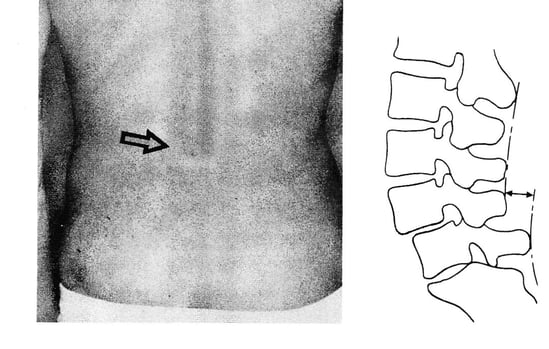

視診/触診 腰椎過前弯、棘突起陥凹/階段状変形(L4/L5)

触診にて階段様変形が確認できる場合やすべりが顕著な場合には、時間を要しますが、正しい生活習慣と施術にて改善していくことが多いです。

階段状変形が触診で確認できたので、富士山は厳しいと思っていましたが、私としても驚きと共に嬉しい結果となりました。

【画像】腰痛テキスト 川端正也著 南江堂 2000年

上の画像は本人のではありませんが、椎間板が変性劣化し腰椎が前方に滑っている画像